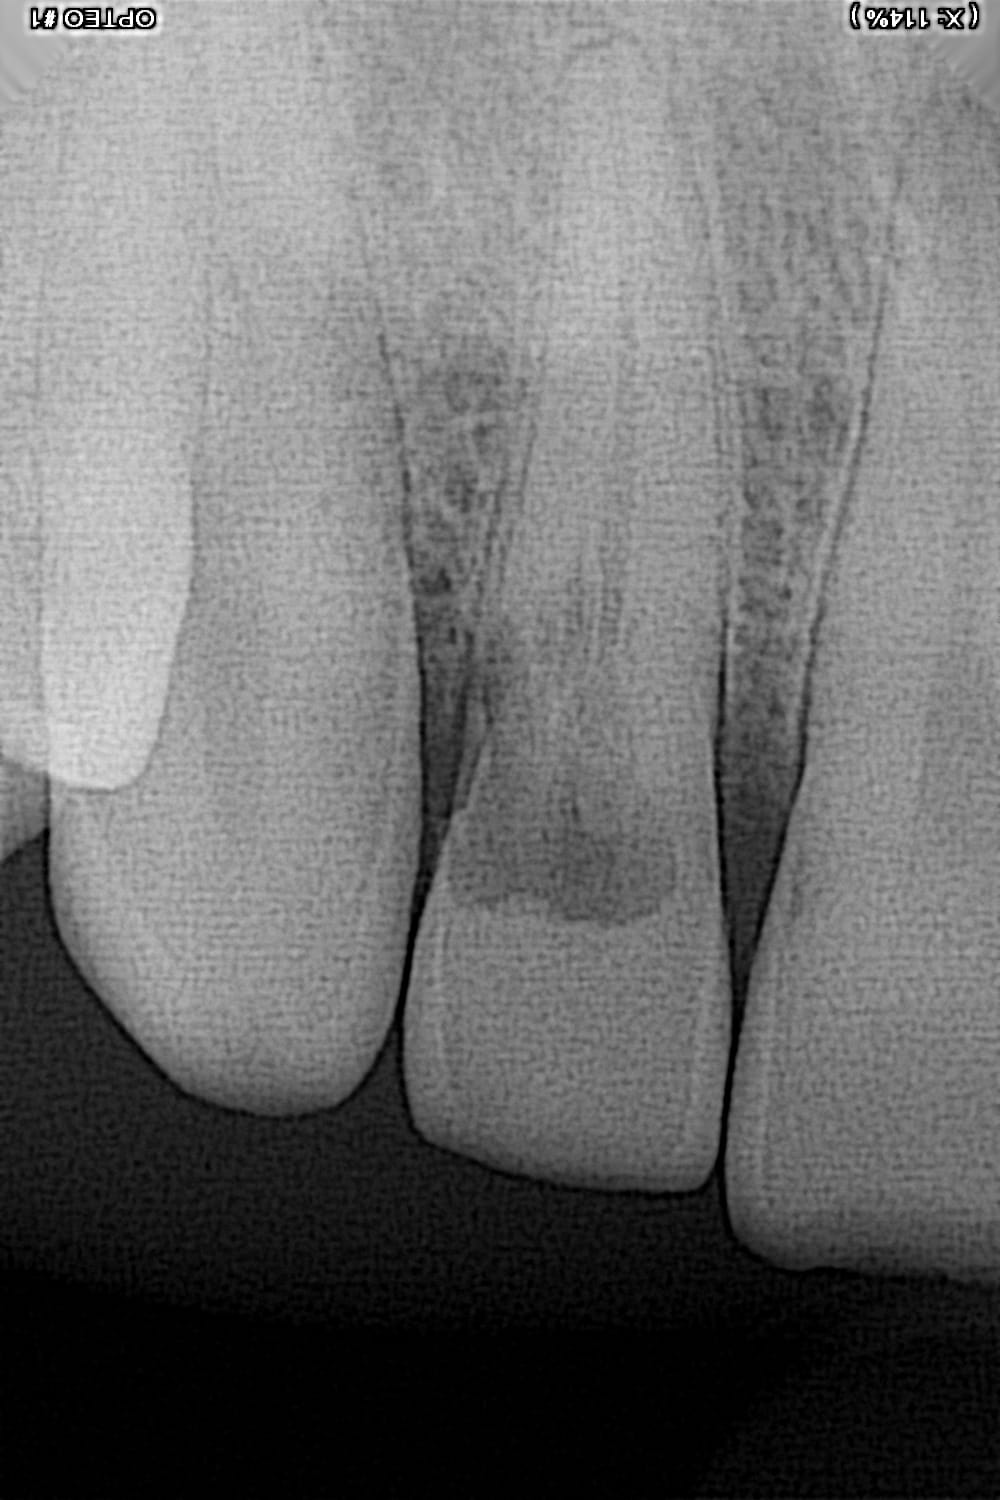

Découverte fortuite, petit puis infra gingival au collet. Dent asymptomatique. Y a t'il autre chose à faire qu'une extraction et un implant?

Découverte fortuite?

La résorption est sous l’os.

Tu ne peux pas stabiliser et la dent sera cassante.

Le patient n'est pas jeune, il a 43 ans. Mais a part ça, sa denture est nickel. Découverte fortuite, j'ai fait une radio parce que la dent était un peu rosée effectivement. La gencive est clean. Ce sera sûrement extraction implant alors. Merci